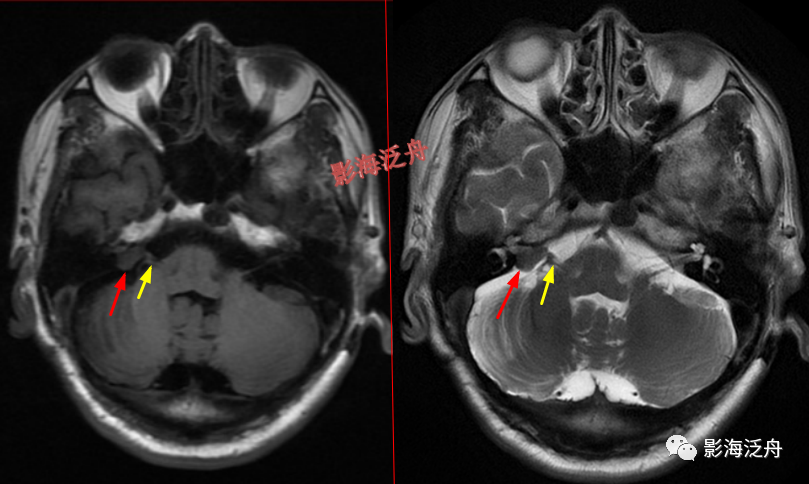

延髓左侧小梗死灶。这种斑点状的梗死灶漏诊也非常多见,患者症状一般不明显,我自己漏诊过两次。小的梗死灶多见于脑干、侧脑室周围,大脑皮层区一般不多见。因此,重点区域进行细致观察,可以减少此类疾病的漏诊。

这个烟雾病的病例在之前的文章中(颅脑MR平扫中极易漏诊的点!)已经提到过,再拿出来复习一下。

脑膜炎

患者,桥前池内可见异常增多的血管影(红箭),正常人的桥前池因为脑脊液流动产生的伪影也可以看到池内絮状低信号(绿箭),但不如右侧患者的明显,这个观察起来比较困难,就如在腹部CT

上观察患者是否存在肝脏肿大一样,需要一个经验积累的过程。黄

箭指基底动脉,蓝箭指三叉神经。